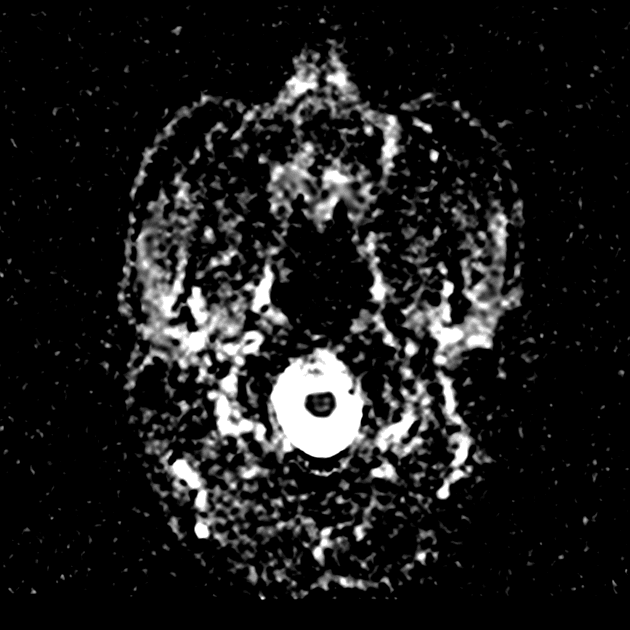

Axial ADC

- Có một phần hạn chế khuếch tán (diffusion restriction) ở vùng ngoại vi, nhưng không có ở trung tâm.

Lesion "hoàn hảo" bắt thuốc dạng viền, nhưng không phải là áp xe não (do không có hạn chế khuếch tán ở trung tâm trên hình ảnh khuếch tán – DWI và lượng phù tương đối ít). MAGIC DR là từ viết tắt gợi nhớ hữu ích cho hình ảnh này.

- "Các khối u thứ phát bắt thuốc dạng viền có thể bắt chước áp xe não trên hình ảnh, nhưng hạn chế khuếch tán ở trung tâm gợi ý áp xe hơn là u thứ phát."